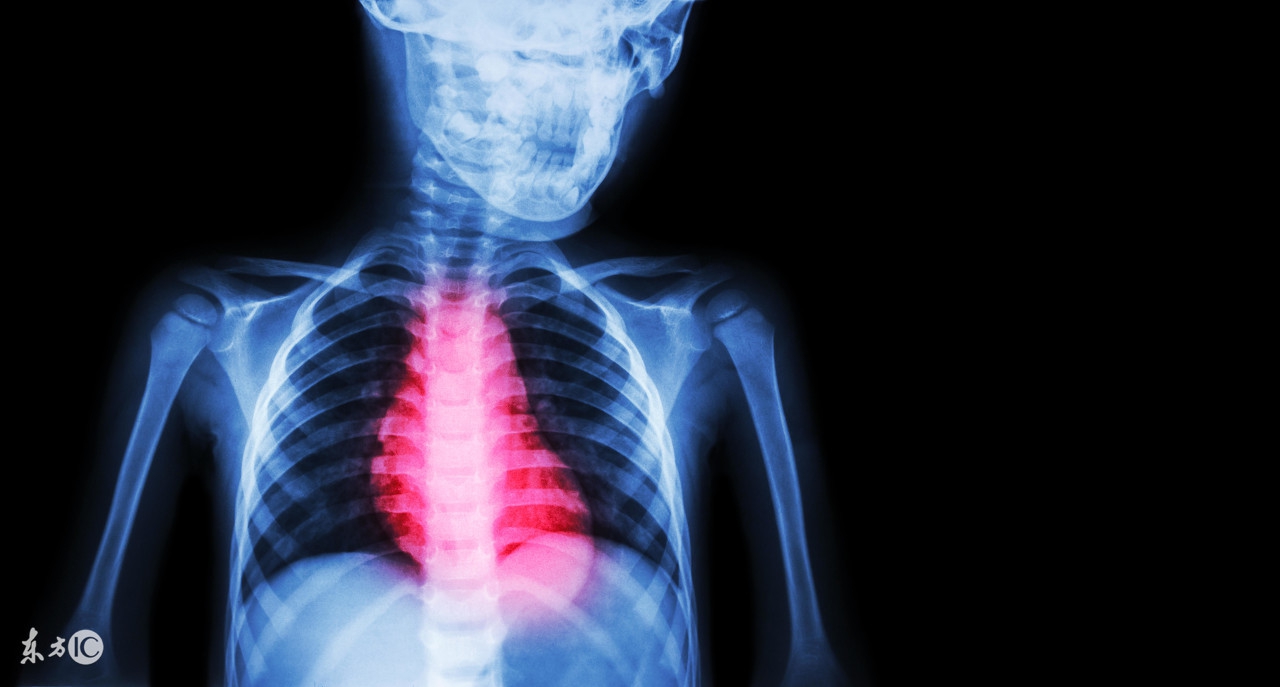

患有心肌缺血的患者朋友在活动量较大或是神经紧张的时候,身体会出现胸闷的情况的,会感觉呼吸不上来,有的时候会有紧缩的疼痛感,还会出现莫名的心悸心慌感的。会有突发心动过缓或是晕厥现象。另外心肌缺血还会有发生心肌梗塞和猝死的危险,因而,因此我们要了解一些关于心肌缺血治疗方面的知识才行的。

第一招、积极治疗:因为心肌缺血对人身体危害很大,且该疾病多发生在老年人身上,老年人身体机能各方面能力下降,患病后十分危险,因此我们要在发现一些心肌缺血症状时及时的去医院治疗。心肌缺血治疗主要是以扩张血管、改善心脏供血为主要。